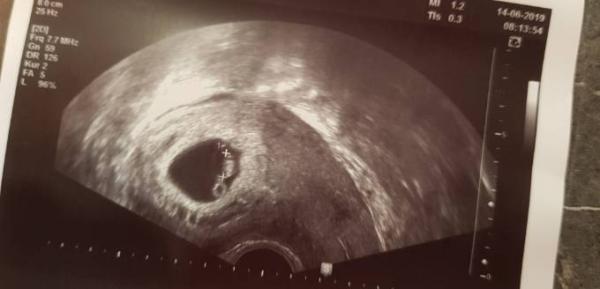

Guten Morgen ihr lieben, heute hatten wir unseren nächsten US Termin. Ach war ich aufgregt aber so geht es euch allen sicherlich Krümelchen wächst und gedeiht blubbert auch so kann man sich gut ins Wochenende Starten auch wenn es bei mir Arbeiten heißt ich wurde 5 Tage zurück gesetzt aber das ist ja nicht Wild. Wünsche euch allen ein tolles Wochenende und am 26.6 bin ich wieder dran

Bild zu Zurück vom FA - Forum für Januar - Mamis